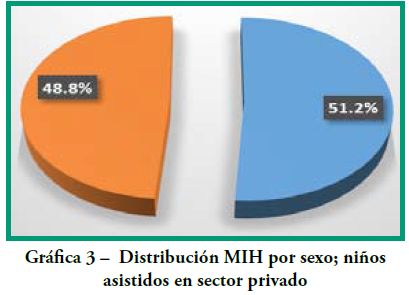

Los resultados intragrupo se representan en las Gráficas 1-6.

Distribución MIH según género

Grupo 1 Sector Privado (Gráfica 3):

masculino (21) 51.2%

femenino (20) 48.8%